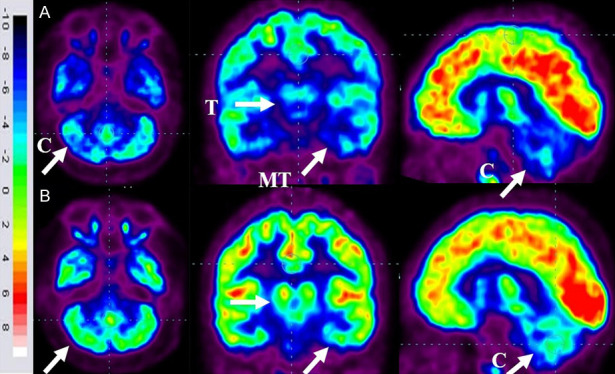

86名患者的家長同意在干預(yù)6個(gè)月后重復(fù)進(jìn)行FDG-PET CT掃描以進(jìn)行比較分析。干預(yù)前,這些患者的FDG-PET/CT掃描顯示雙側(cè)內(nèi)側(cè)顳葉皮層、丘腦和小腦的代謝活動降低[代謝減退]。此外,它們還表現(xiàn)出尾狀頭、殼核、眶額皮質(zhì)和前額葉皮質(zhì)的代謝活動增加(代謝亢進(jìn))。

干細(xì)胞移植六個(gè)月后,所有患者的大腦活動均得到改善。此前,代謝低下區(qū)域[內(nèi)側(cè)顳葉皮質(zhì)、丘腦和小腦]顯示FDG攝取增加,而代謝亢進(jìn)區(qū)域[尾狀頭、殼核、眶額皮質(zhì)和前額葉皮質(zhì)]顯示FDG攝取減少(圖6)。在進(jìn)行T檢驗(yàn)時(shí),發(fā)現(xiàn)干預(yù)前后這些區(qū)域的平均SUV出現(xiàn)了統(tǒng)計(jì)學(xué)上的顯著變化[P<0.05]。

圖6:ASD患者在細(xì)胞治療前和細(xì)胞治療后6個(gè)月進(jìn)行的FDG-PET/CT大腦掃描的代表性圖像。

A.頂行:標(biāo)有箭頭的藍(lán)色區(qū)域表明代謝低下。B. 下排:用箭頭標(biāo)記的綠色區(qū)域表明細(xì)胞移植后新陳代謝得到改善。

FDG PET CT大腦掃描被用作接受多劑量細(xì)胞移植的患者的額外結(jié)果測量。它用于監(jiān)測細(xì)胞水平干預(yù)的效果。這種功能性神經(jīng)影像技術(shù)利用18-FDG來研究大腦的代謝活動。我們對86名患者進(jìn)行了FDG PET CT掃描腦部的比較研究,結(jié)果證明了其對新陳代謝的平衡作用。代謝低下的區(qū)域顯示代謝增加,而代謝亢進(jìn)的區(qū)域顯示代謝減少。